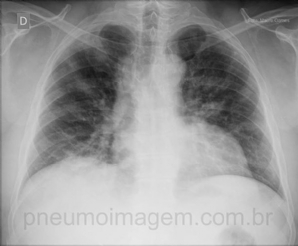

CASO CLÍNICO #22

Qual o nome desse sinal e o que ele significa? Deixe seus comentários abaixo. *** What is the name of the sign and what it means? Leave your comment below.